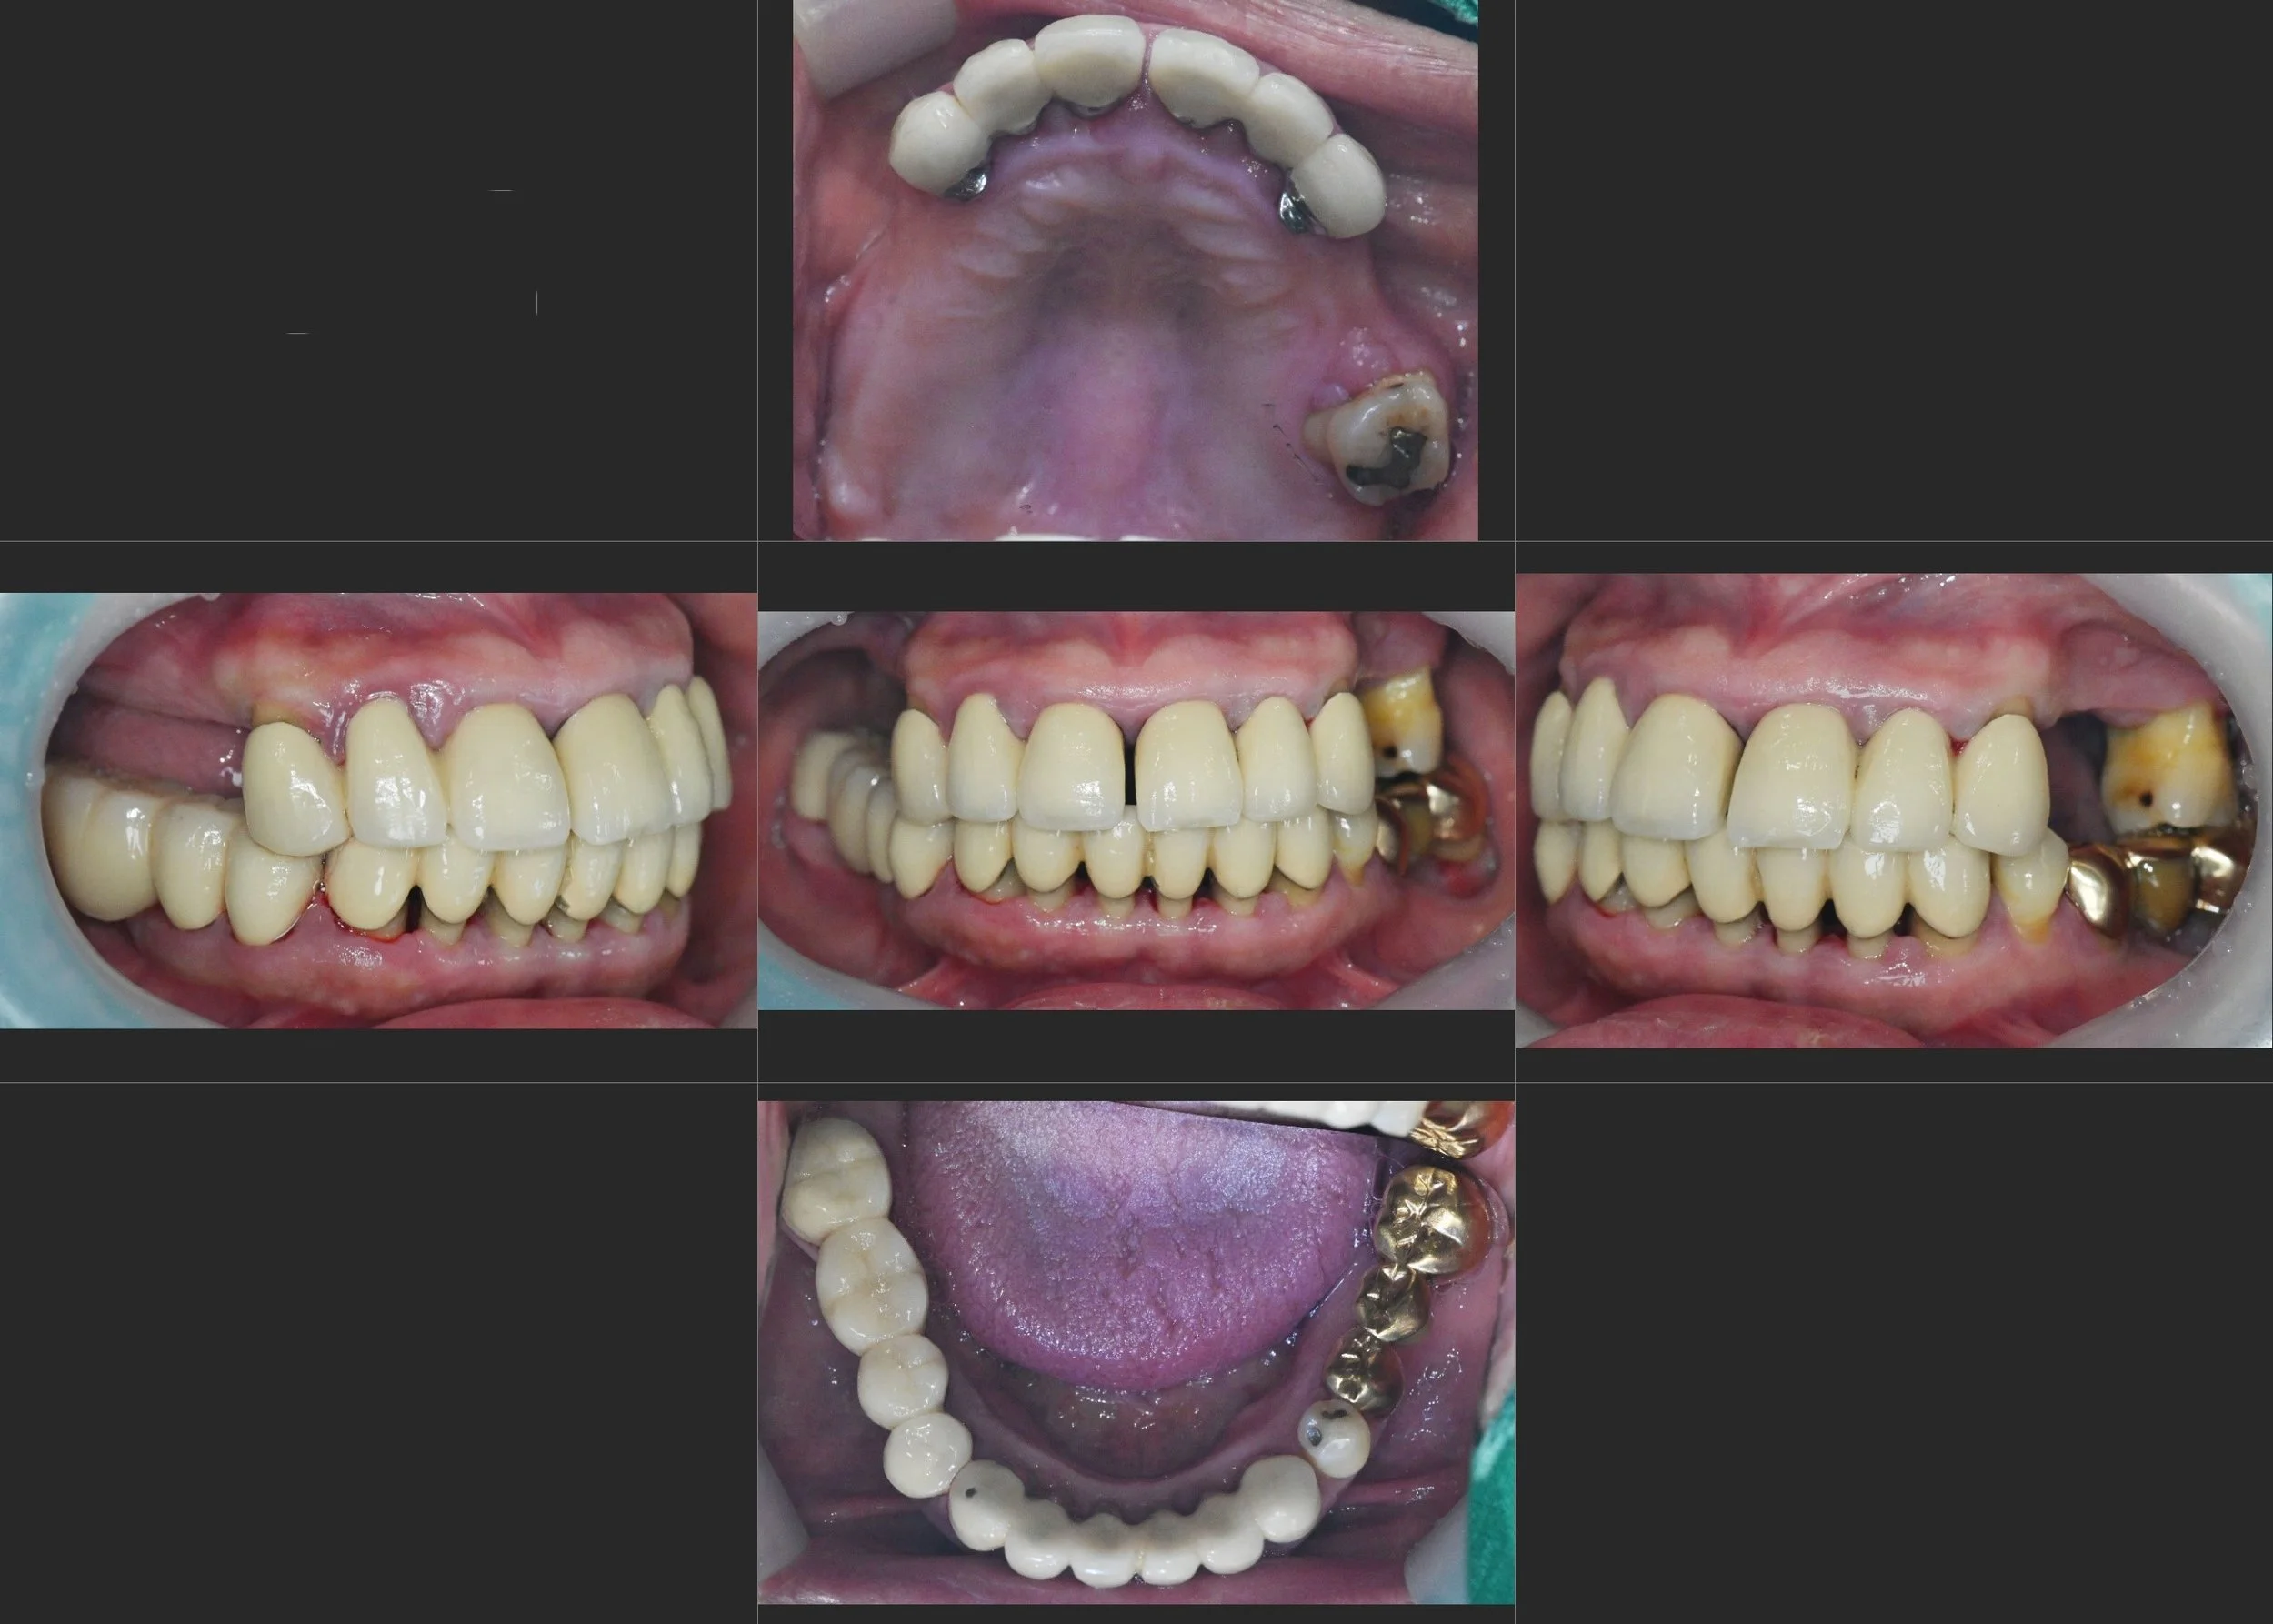

39. Comprehensive Full-Arch Rehabilitation: Overcoming Severe Bone Atrophy and Occlusal Collapse

Management of Generalized Alveolar Resorption and Failing Existing Prosthetics in a Female Patient in her 60s. A Systematic Approach via Bilateral Sinus Augmentation and VDO Elevation.